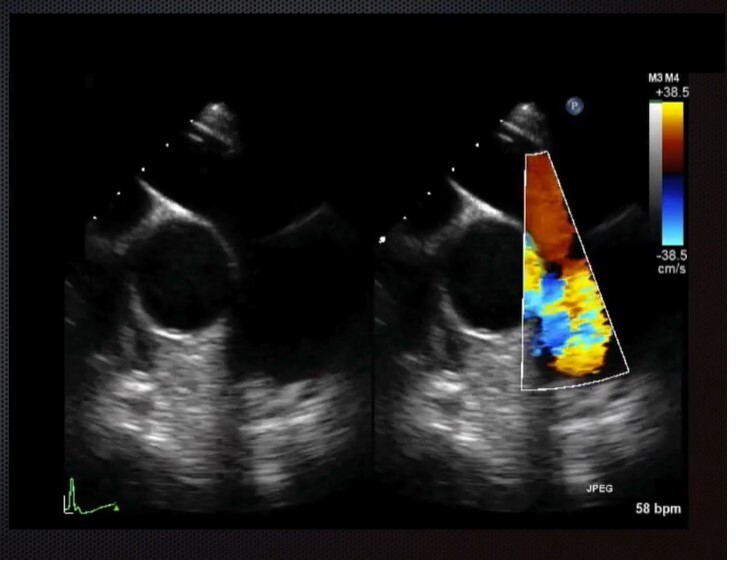

Mid-Esophageal RV Inflow-Outflow View - AV, RA, RV, tricuspid valve, pulmonic valve. Advance probe slightly from MEAVSAX and then rotate probe clockwise to center tricuspid valve. Multiplane to between 60-90 degrees. Good for TV pathology, PV pathology, and right heart function.